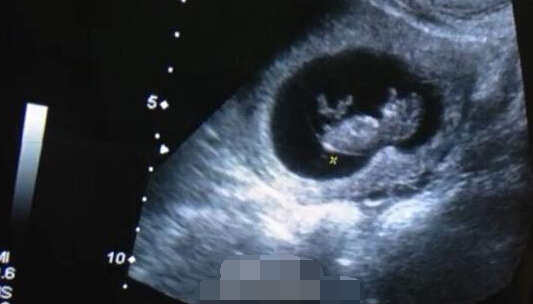

7月26日做的b超检查证实欢欢怀孕了,胚胎长3.4厘米.

代孕母猫妊娠期间的b超图像.青岛农业大学供图

兽用无线b超检查羊怀孕不同时期超声影像二,兽用无线b超gdf-c80技术